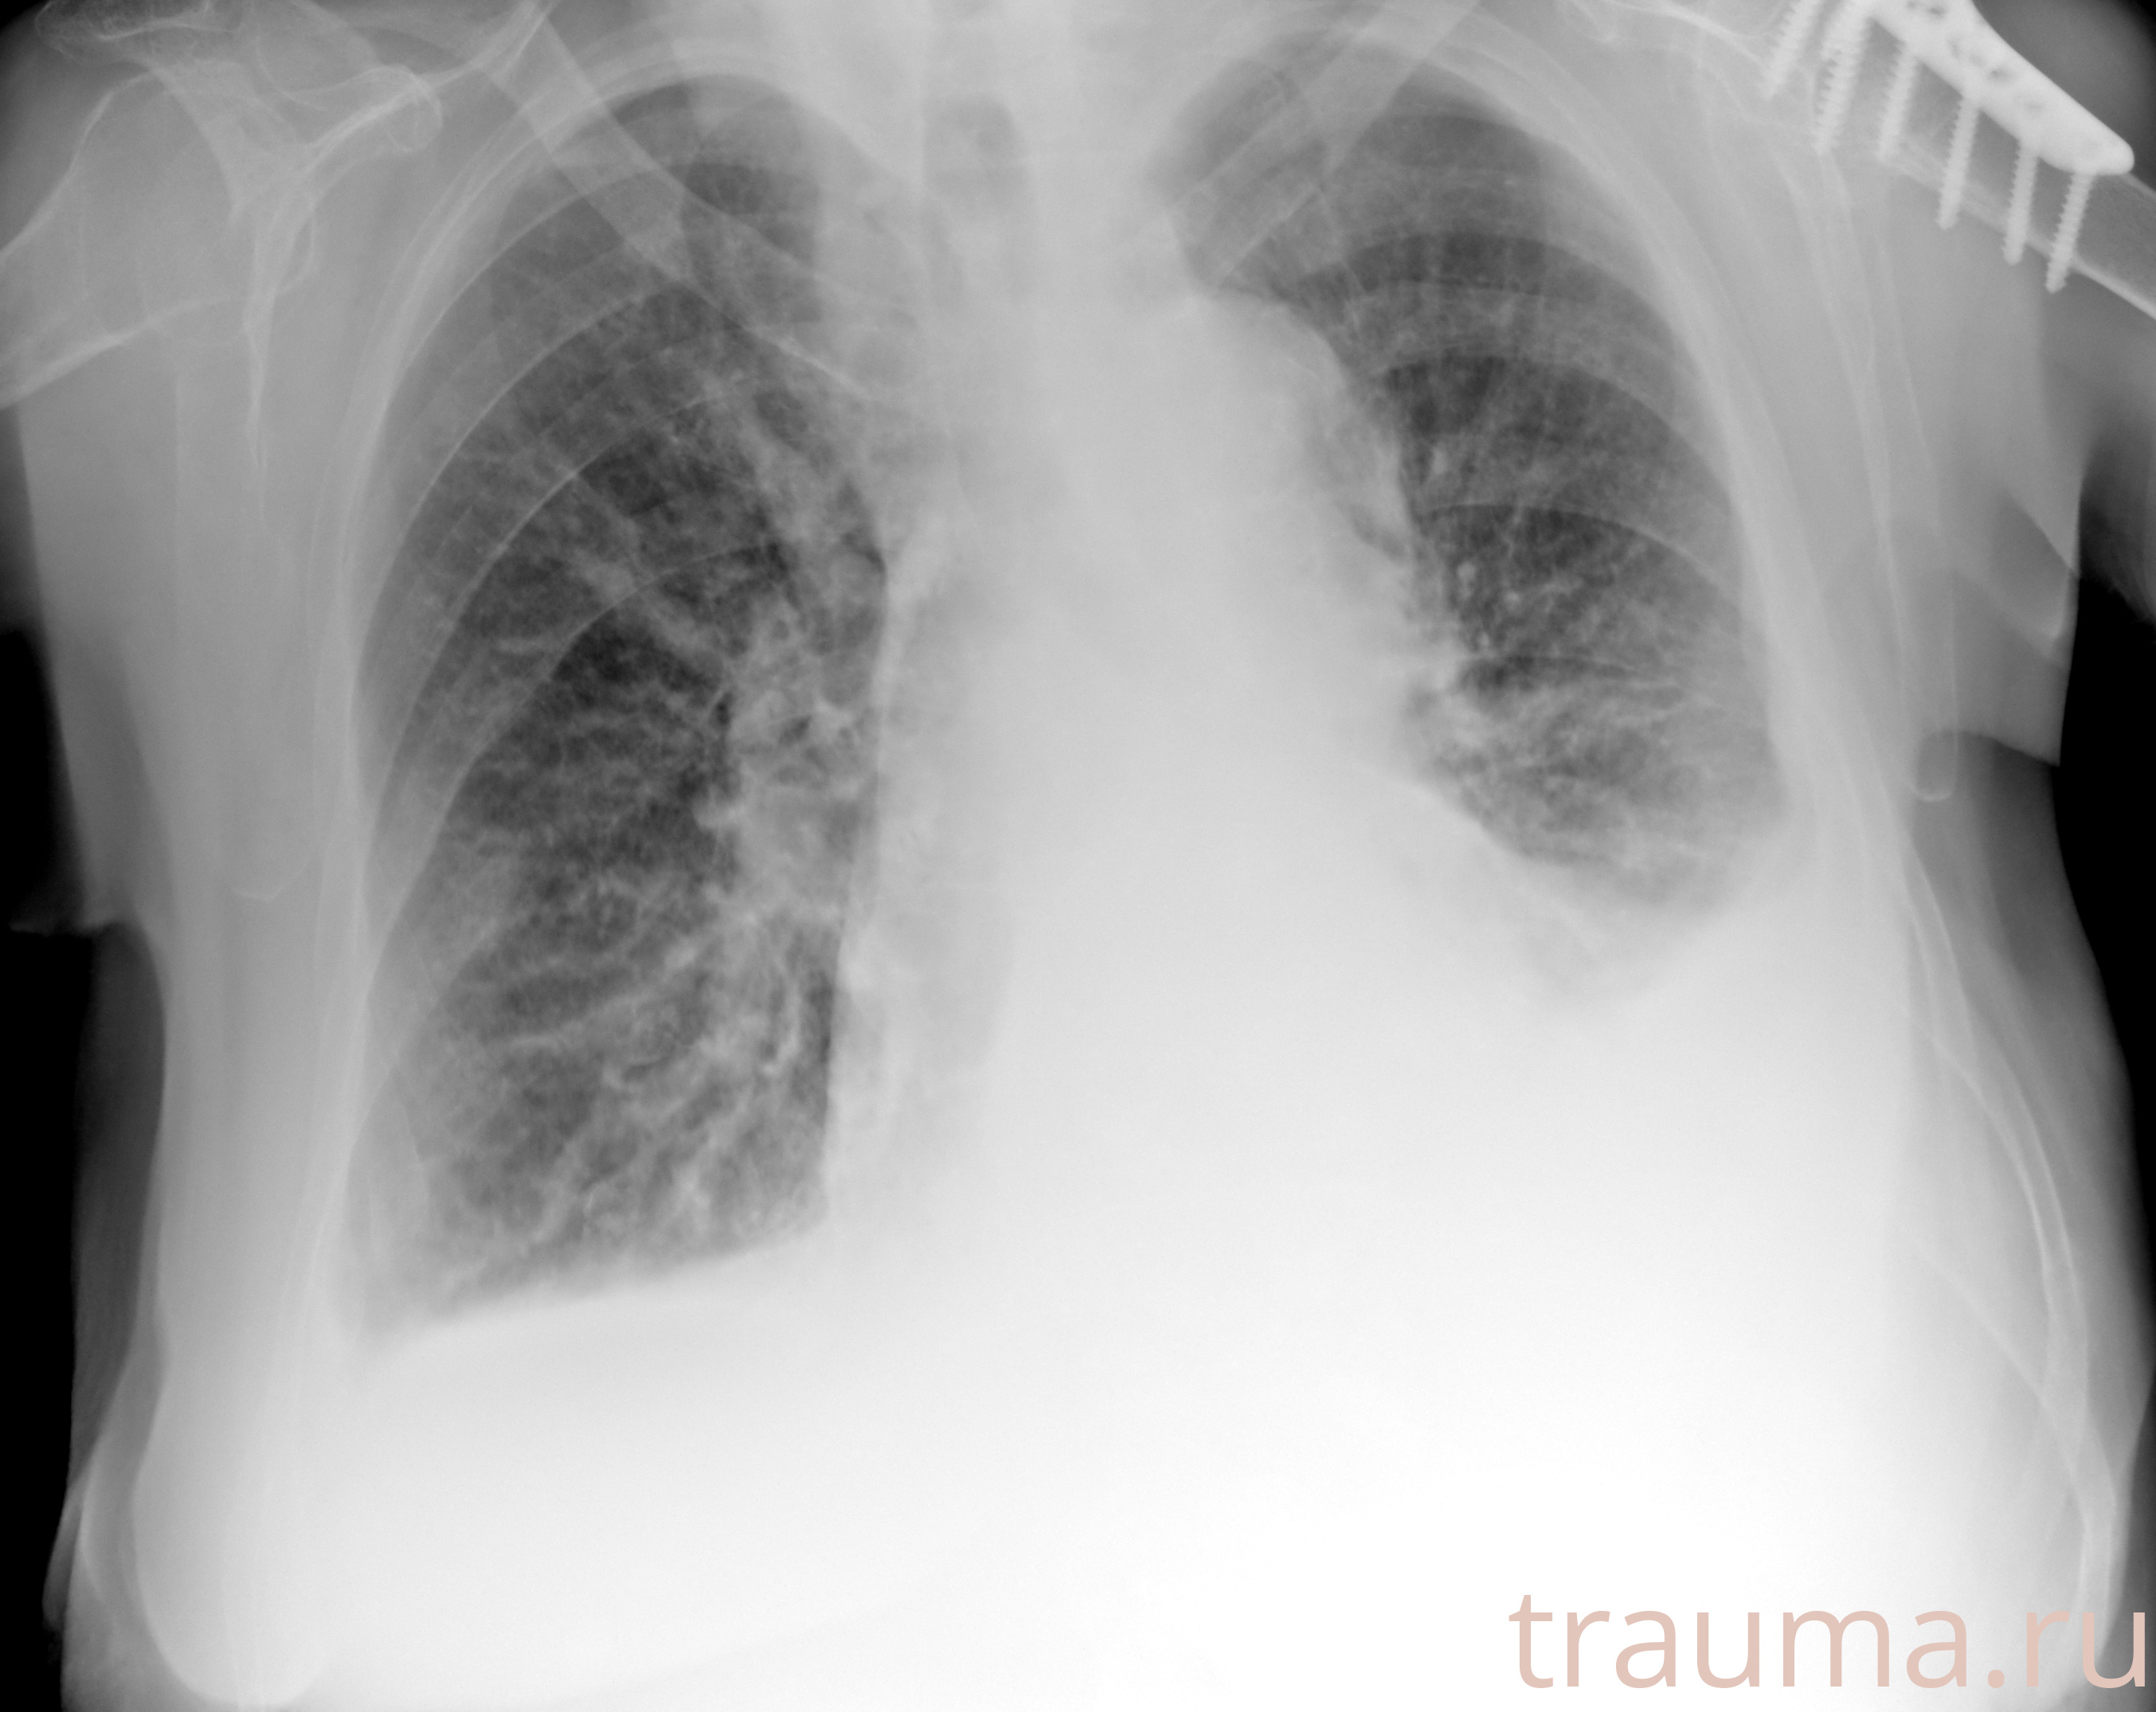

Рентген на дому: по вашему адресу приезжает врач-рентгенолог, травматолог-ортопед с мобильным рентгеновским аппаратом, проводит диагностику травмы или заболевания, делает необходимые рентгенограммы, дает рекомендации по дальнейшему лечению. Получить качественные снимки в домашних условиях возможно благодаря уникальной методике, разработанной МосРентген Центром для института  Склифосовского

при переломе шейки бедра и пневмонии от компании МосРентген Центр - партнера Института имени Склифосовского